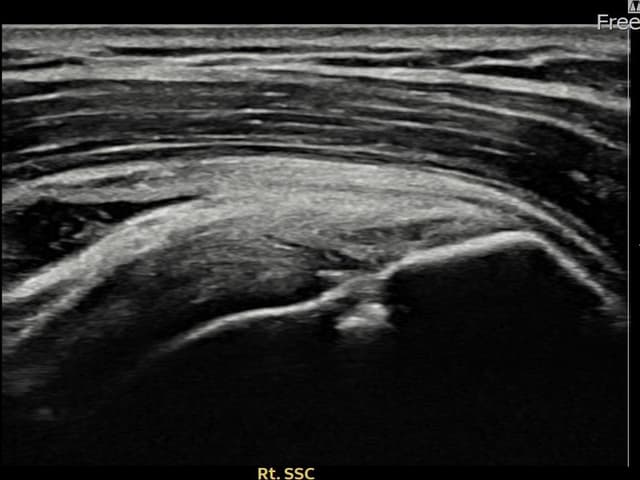

[촬영시기:22.08.29~22.12.23]

[어깨인대 축소봉합술] 우측 어깨 전방 통증과 팔 내회전 제한으로 내원하셨습니다.